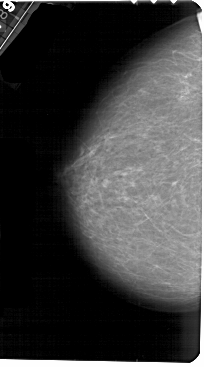

A_1426_1.RIGHT_MLO

RIGHT_MLO LINES 5491 PIXELS_PER_LINE 3031 BITS_PER_PIXEL 12 RESOLUTION 43.5 OVERLAY